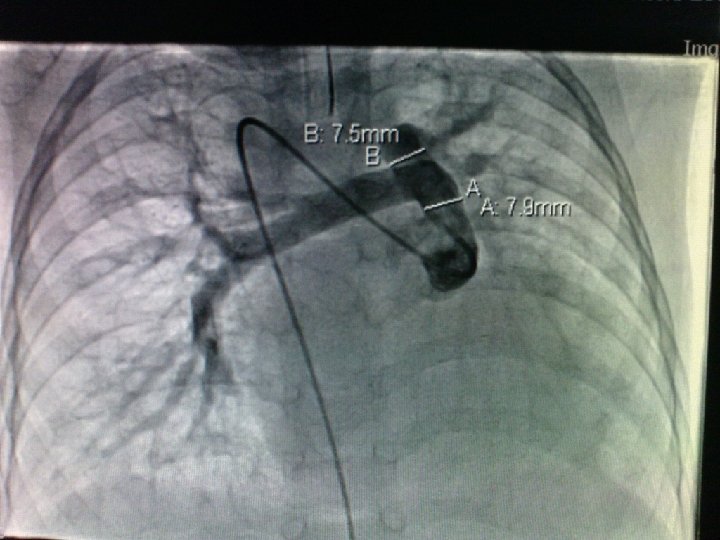

Completion of TCPC Surgical technique: How I do it? On CPB or Off-pump Dissection of IVC and PA Tailoring the PTFE conduit (at least size 16 mm should be selected for adequate IVC flow) Anastomosis: the IVC anastomosis is done first. Side-to-side fenestration